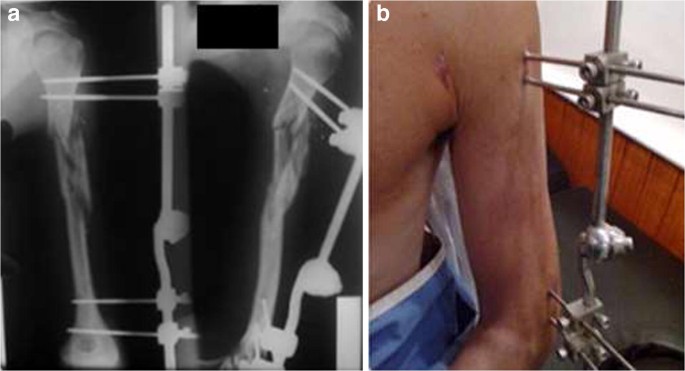

External Fixation involves placing metal pins or screws into the bone fragments on either side of a fracture, which are then connected to an external frame outside the body. This frame holds the bones in the correct position, ensuring stability as they heal.

- Pin Placement: Pins or screws are inserted through the skin into the bone on either side of the fracture.

- Frame Attachment: The pins are connected to a stabilising frame outside the body, which holds the bone fragments in alignment.